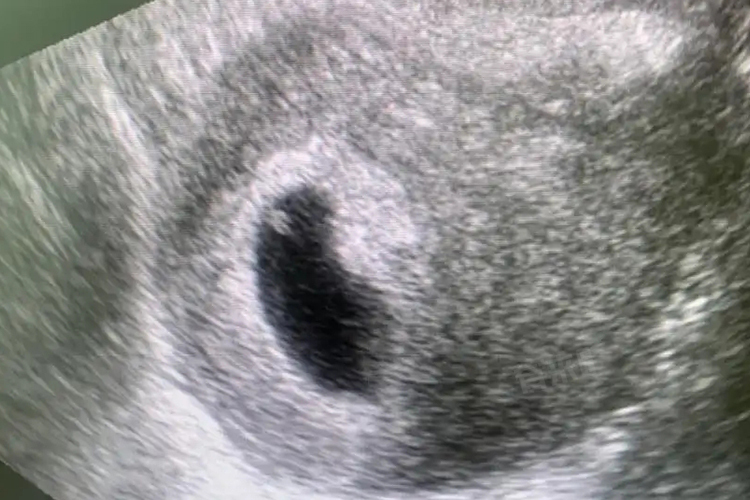

1、卵黄囊的直径和形态:正常卵黄囊呈圆形,壁薄,边缘光滑,内为无回声,直径一般在0.5-0.6cm。如果卵黄囊皱缩,直径≤0.3cm或过大,直径≥1.0cm,或者缺如,都可能提示胚胎发育不良。

2、后续检查:卵黄囊出现后,还需要通过后续的超声检查来确认是否有胎心及胎芽的出现,胎心及胎芽的出现才能真正代表胚胎存活并处于稳定状态。